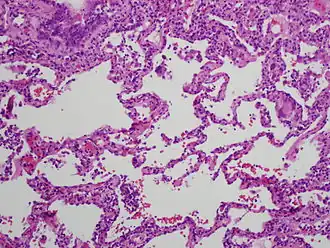

![]() Esta es una fotomicrografía a gran aumento de una biopsia pulmonar (tinción hematoxilina-eosina). Muestra una moderada expansión de los tabiques alveolares (intersticio) debida a linfocitos. Una célula gigante multinucleada, vista dentro del intersticio a la derecha de la imagen medio camino hacia abajo, es una pista importante hacia el diagnóstico. | ||